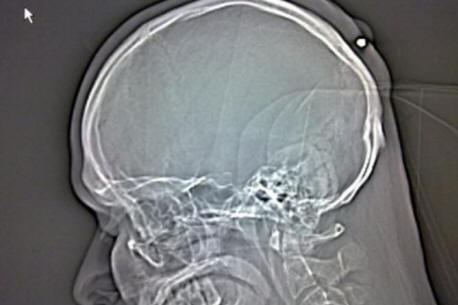

Amikor a kórházra utalt, Autullo megtagadta ezt az orvosok megmutatták neki: a röntgen során egyértelmű volt egy nyolc centiméter hosszú vasszeget ragadtunk be közvetlenül a koponya belsejébe doboz Dante. Mielőtt a mentők elvitték az Autullót egy másik klinikára Dante egy fotót tett közzé a Facebook oldalán röntgenkép.